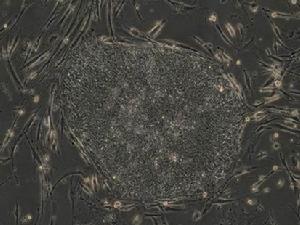

另外一個科研小組則更為大膽,他們跳過了胚胎階段,把老鼠胰腺內的一種成熟細胞———外分泌細胞,直接改造成了另外一種類型的細胞———貝塔細胞。

第3支研究團隊另闢蹊徑,跳過幹細胞的階段,直接將成熟老鼠的胰臟外分泌細胞,轉化成負責製造胰島素的beta細胞。以上3項研究所製造的新細胞株,有助認識疾病發展和研究治療藥方,當科學家能更精細、有效和安全地掌握細胞工程技術,便可利用病人的自身細胞治病,甚至培育器官。